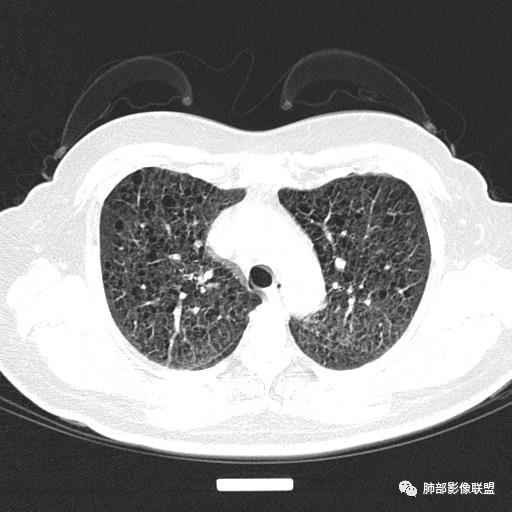

中年女性,不吸烟

双肺弥漫囊腔,累及肋膈角,囊腔形态相对规则单一。

CT平扫示双肺弥漫分布大小不等囊状薄壁透光区,无内、中、外带分布差异,间质稍示增厚。拟LAM

中年女性育龄期妇女,咳嗽气喘,无吸烟史,有苯吸入史。影像:双肺弥漫均匀小囊腔,无明显分布优势,囊腔形态欠规则,壁薄,部分囊腔边缘血管征,伴双肺弥漫磨玻璃影,无结节,考虑lam,鉴别苯中毒肺损伤,囊腔多有分布优势,小叶中心分布为主,形态规整等

中年育龄期女性,双肺多发含气囊腔弥漫性分布,囊间肺组织结构正常,常规考虑Lam

女,46,活动性气喘1年。苯吸入史半年。胸部CT:两肺弥漫囊腔,上至肺尖,下至肋膈角,形态类似小囊腔。考虑:LAM,鉴别LIP,BHD,PLCH等。

双肺弥漫大小不一薄壁含气囊腔,囊间肺组织正常,正常肺背景,肺尖肺底受累;青年女性,气喘,支持LAM

CT表现:双肺弥漫大小不等的薄壁囊腔,囊壁<2mm,外形规则,血管影多位于囊腔周围,囊腔之间肺组织正常,随着疾病进展到晚期,囊腔变大、增多,不可胜数,囊腔可融合成较大的囊,与肺气肿相似,形成间质性肺纤维化。部分病例可出现结节影。